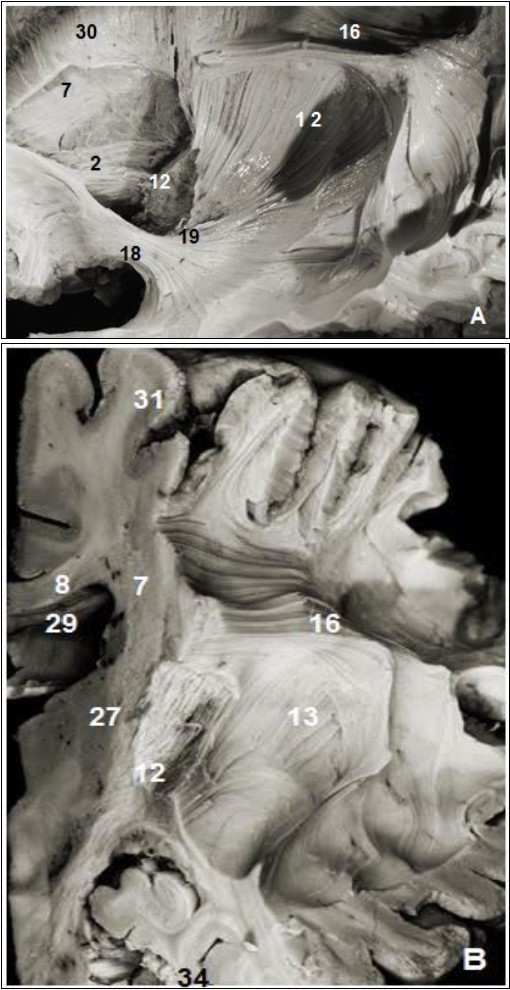

The internal capsule was exposed after the excision of the putamen and globus pallidus which were perfectly identifiable. The abscission of the outermost fibers of the internal capsule situated approximately 26 mm from the cerebral cortex and the head of the caudate nucleus exposed thalamic radiations (Figure 3).

Figure 4.(A) Lateral view of left cerebral hemisphere after dissection and (B) coronal view. 2. Anterior thalamic radiation, 7. Subependymal stratum, 8. Corpus callosum, 12. Internal capsule, 13. External capsule, 13. SLF, 15. Corona radiata, 16. Uncinate fasciculus, 19. Inferior frontal occipital fasciculus, 27. Putamen, 28. Globus pallidus, 29. lateral ventricle, 31. Parietal pole, 34. Temporal pole.

The inferior occipitofrontal fasciculus (Figure 2, Figure 4) closely attached to the previous fasciculus was composed of fiber bundles connecting the frontal lobe to the temporal, posterior parietal and occipital lobes. The IOFF is shaped somewhat like a flattened tape and is composed, as the uncinate fasciculus, of three parts: frontal, insular and parietal temporo-occipital segments.

The insular segment was fully exposed after the ablation of the uncinated bundle and courses medial to the external and extreme capsule and above the uncinate fasciculus. This segment was on average 2 mm thick and 8.8 mm wide.

The parietal temporo-occipital segment is about 20 mm wide stretching from the amygdala to the pulvinar and geniculate bodies at the height of the ventricular atrium.

The fanning frontal segment is located at the height of the frontal horn of the lateral ventricle. The frontal distribution of the inferior occipitofrontal fasciculus stretches to the whole of Broca's area. This frontal end was located 25 mm away from the cortex of the lower frontal gyrus. It is the second fasciculus connecting the frontal and the occipital lobes, and is thin at the frontal end.